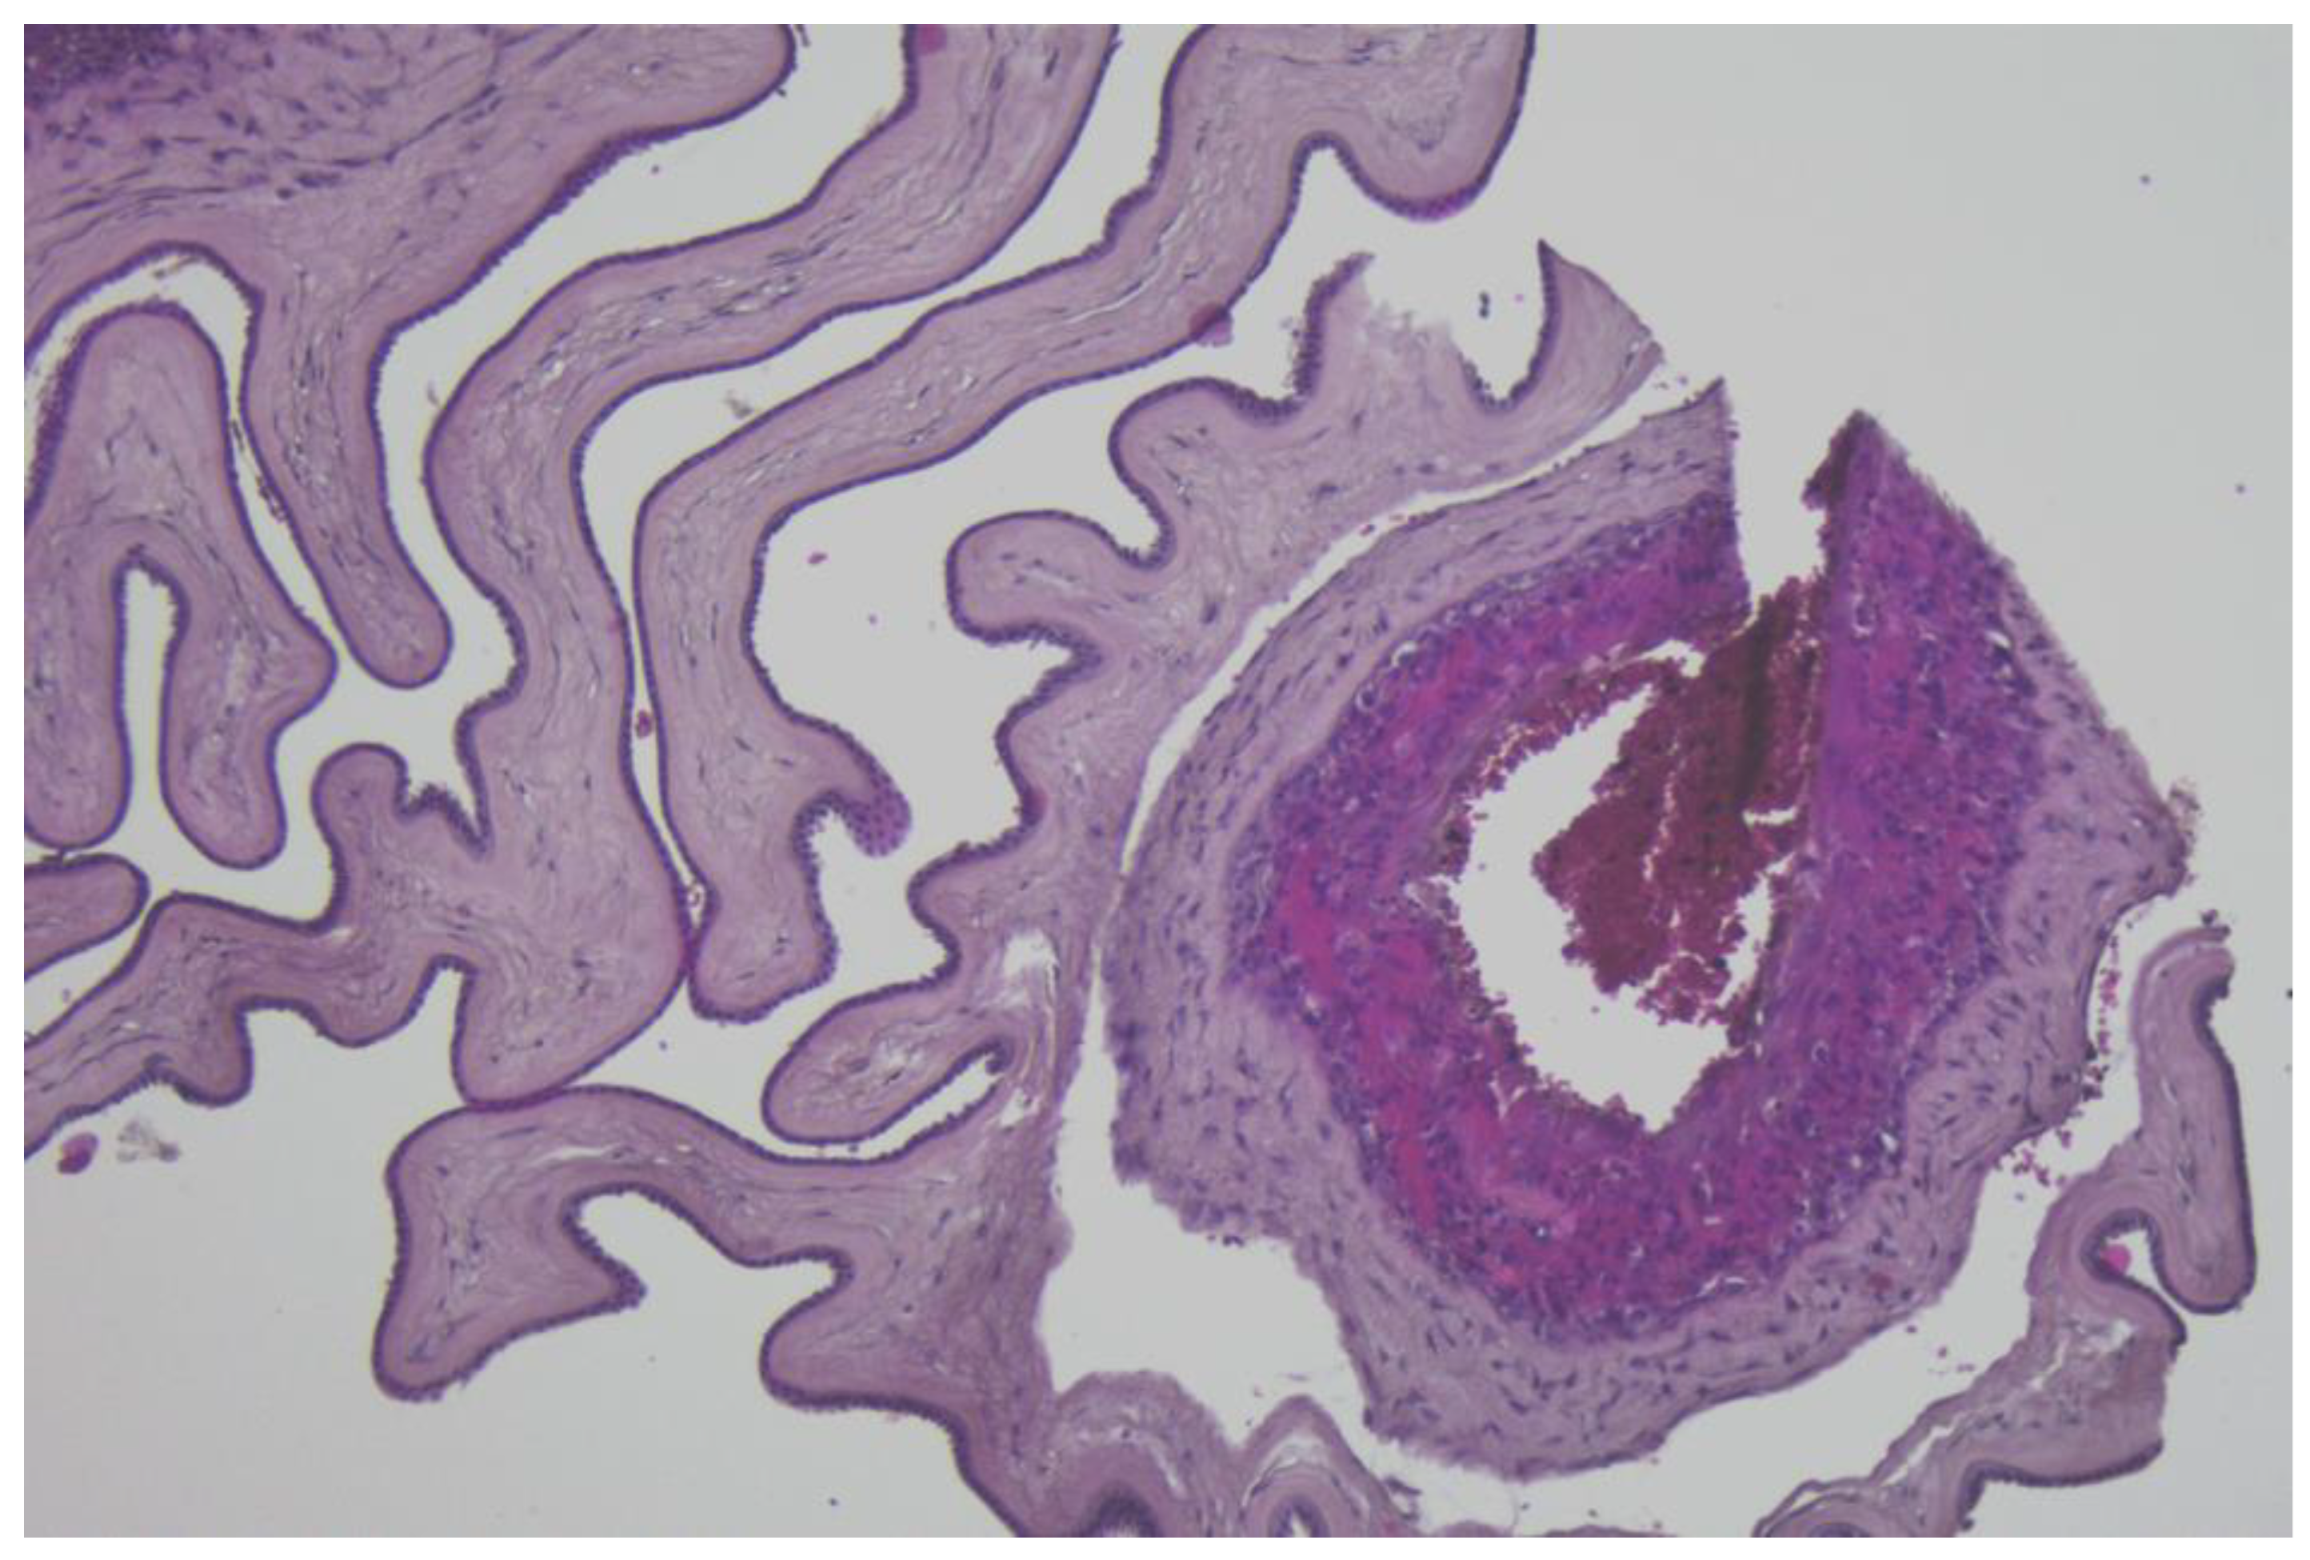

The immunohistochemistry analysis of the umbilical cord, amniotic membranes, and placental fragments from pregnant patients with COVID-19 failed to demonstrate positivity for the following markers: CD19, CD3, CD4, CD8, and CD56. These antibodies were used in order to find the inflammatory cells in the analyzed tissues as follows: CD19 for B cells, CD3 for T cells, CD4 for T helper cells, CD8 for cytotoxic T cells, and CD56 for NK cells. Tissue samples stained with hematoxylin and eosin, as well as immunohistochemical markings, are presented in Figure 1, Figure 2 and Figure 3.

Figure 2.

Histological aspect of umbilical cord section, lacking inflammatory reactions, H&E stain, ×100 magnification.

Figure 3.

Amniotic membrane section, without inflammatory cells, H&E stain, ×100 magnification.

Finally, our immunohistochemistry analysis of umbilical cords, amniotic membranes, and placental fragments retrieved in the third trimester of pregnancy failed to demonstrate positivity for CD19, CD3, CD4, CD8, and CD56 markers. In a recent study by Levitan et al., the authors evaluated 64 placentas using immunohistochemical staining for SARS-CoV-2 nucleocapsid protein, and found that none of the specimens were positive for this marker [52]. Another study that analyzed the immunohistochemical staining of placental specimens for various leukocytes revealed an increased CD68+ macrophage infiltration [53].

We hypothesize that a possible explanation for the lack of immunohistochemical positivity of the evaluated markers in the placenta, umbilical cord, and amniotic membranes could be represented by the fact that SARS-CoV-2 infection occurred in the third trimester of pregnancy for the patients enrolled in the study, and the timeframe from infection to birth was generally short for an intensive local immune response.